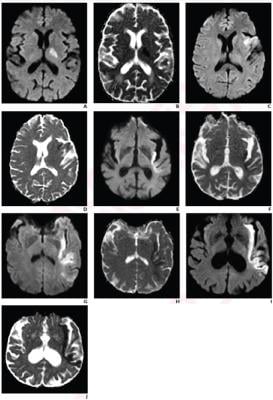

Analyzing a previous clinical trial of acute stroke patients untreated with reperfusion therapies from January 2007 to June 2009, Regenhardt et al. reevaluated 31 trial patients (median age, 71 years; 12 female, 19 male) with anterior-circulation large-vessel occlusion who underwent serial MRI examinations. Two neuroradiologists independently scored PIRI on presentation MRI—mild (0-1), moderate (2), severe (3-4)—based upon length ratios of the insula portion showing restricted diffusion to the insula’s total length. A 90-day modified Rankin Scale (mRS) was also obtained.

Ultimately, in multivariable models controlling for age, large-vessel occlusion location, and collateral pattern, PIRI category was a significant independent predictor of presentation-to-48-hour infarct growth rate (β=1.3) and 90-day mRS ≤2 (OR=0.2). Sensitivity and specificity for predicting 90-day mRS ≤2 were 90% and 84% for mild-to-moderate PIRI, versus 70% and 74% for symmetric collateral pattern.